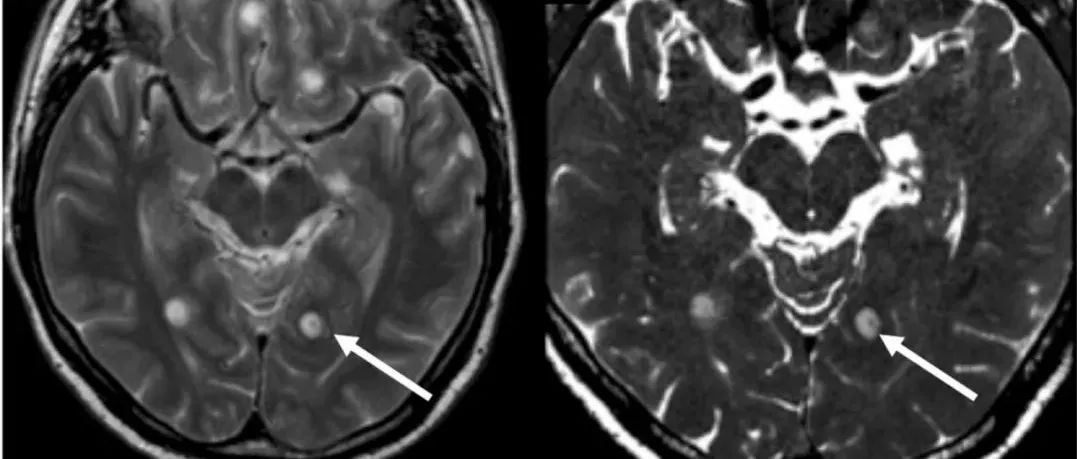

51岁男性,表现为头痛、腿部和手臂感觉异常和癫痫发作。MRI可见多发囊性病灶伴点征(dot sign)和钆强化(图1-2)。(图1:A-B:轴位T2WI可见多发囊性病灶,一个位于左侧枕叶伴点征[箭];C:轴位FLAIR可见大多数病灶周围存在血管源性水肿;D:轴位增强T1WI可见周围和点征强化;点征是囊性病灶内的结节)(图2:A-B:轴位T2WI可见右侧小脑半球2个囊性病灶伴点征[箭];C:轴位DWI显示点征[箭];D:轴位增强T1WI可见结节和点征强化[箭])...